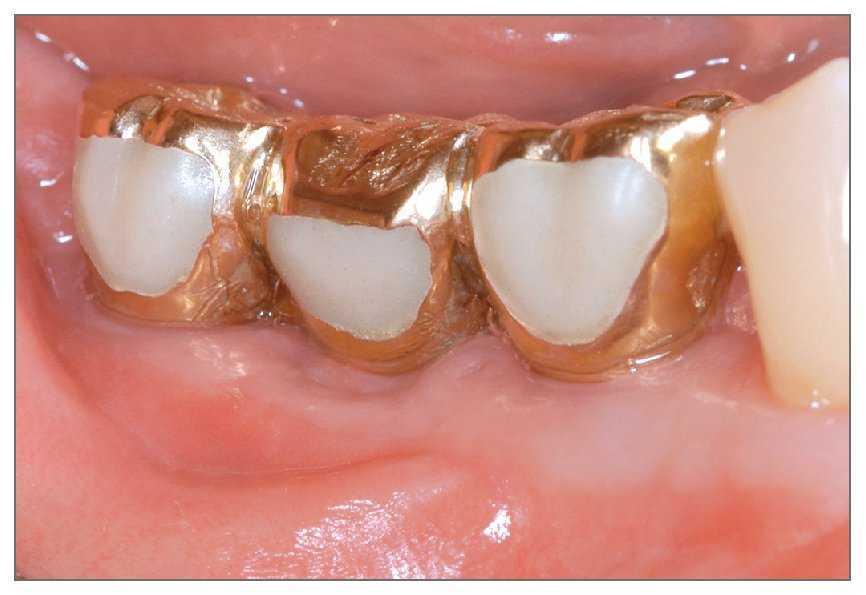

El área injertada curó sin incidencias, y tres meses después de la cirugía se podía observar tejido blando de maduración (fig. 5). La anchura del reborde se había preservado bien y la anchura del tejido queratinizado en el lado vestibular era de 4 mm. Tres meses más tarde se abrió de nuevo la zona de intervención para la conexión de los pilares, y se comprobó que casi todos las roscas se encontraban cubiertas por tejido duro constituido por tejido de nueva formación y material de injerto (fig. 6). La prótesis estaba funcionando bien en la evaluación final, 2 meses después del tratamiento, sin signos de profundidad de sondaje (figs. 7 y 8).

Figura 7 (izquierda). Fotografía clínica mostrando la prótesis en función después de 2 meses.